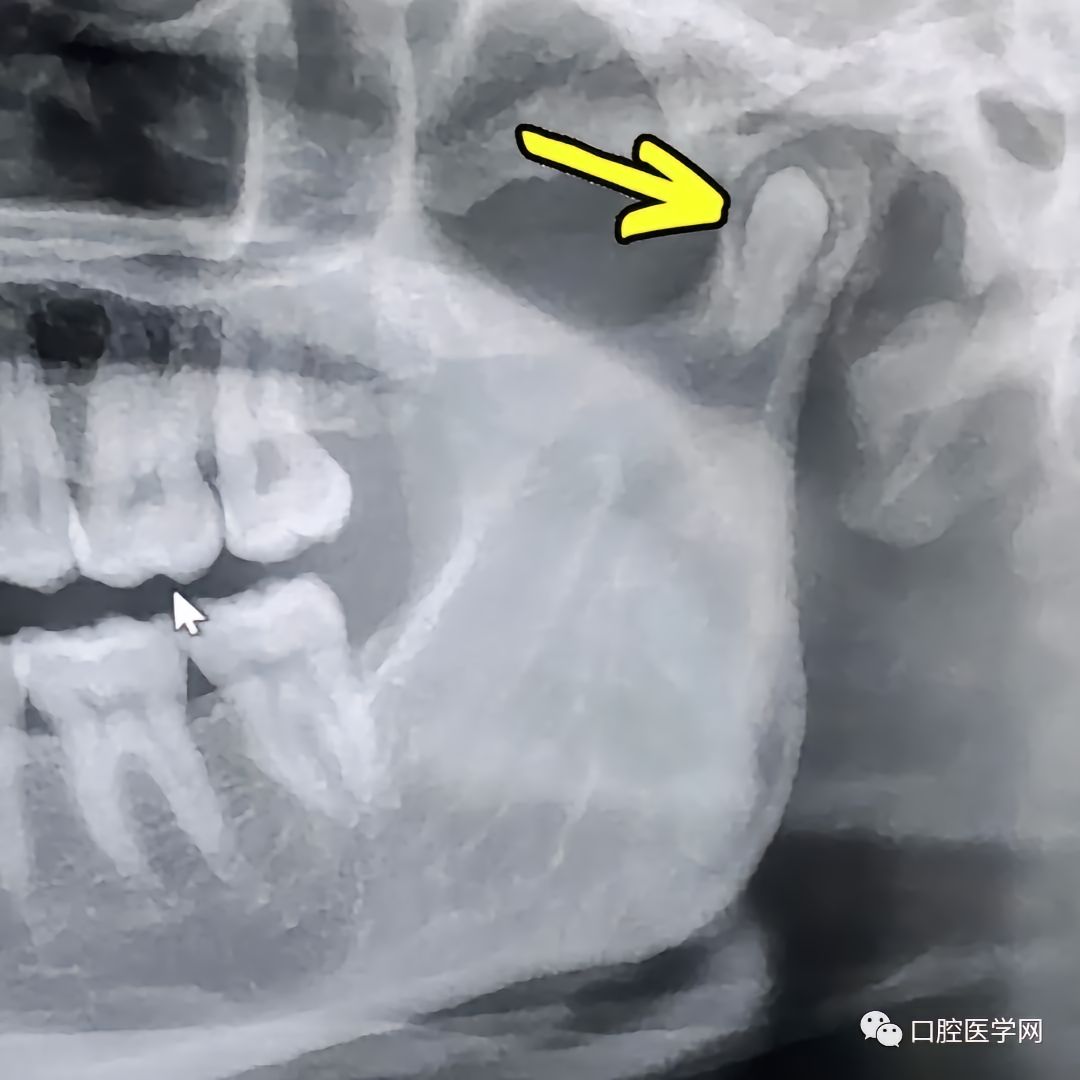

这牙长的也太有个性了

都不敢相信是真的,虽然有图。